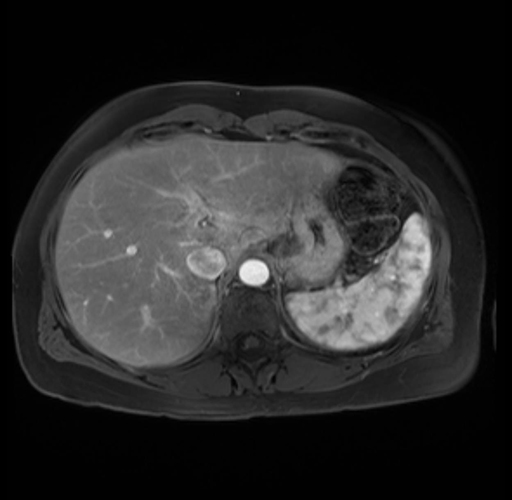

Imaging Analysis

Look through the patient's CT scan to identify any areas of concern for the necessary procedure.

Based on your CT findings, which issue(s) are present and would give reason for "planned slowing down moment(s)" in this case?

Considering a standard distal pancreatectomy procedure, what step(s) of the operation would you do differently in this case?